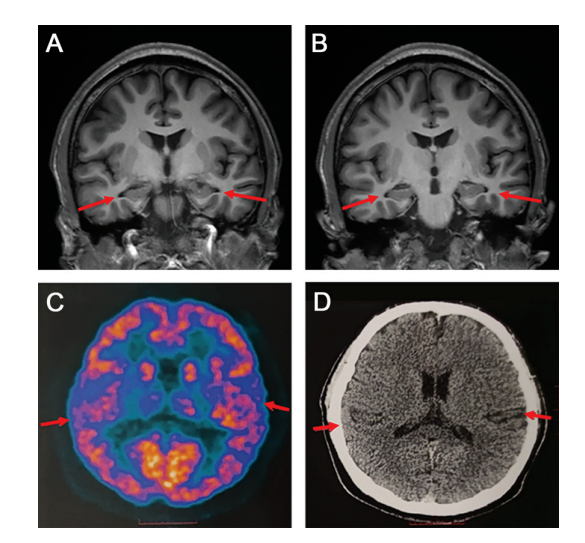

论文中发布的患者脑部影像